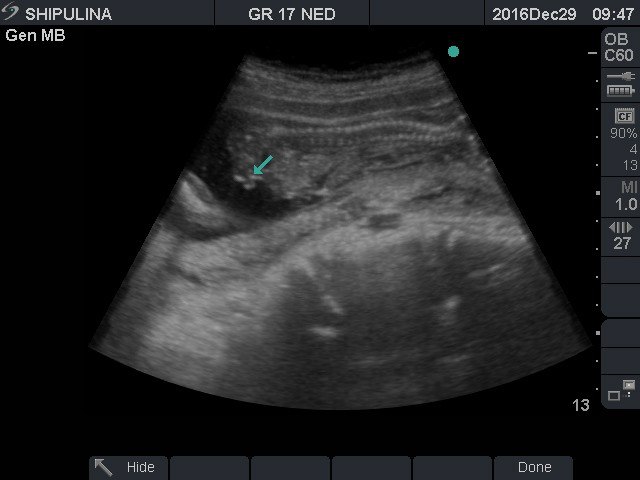

17 недель ровно.мальчик